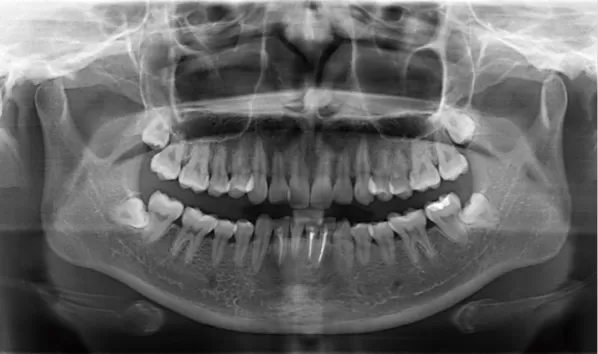

X-rays before treatment

[Panoramic Radiography/Lateral Cephalogram]